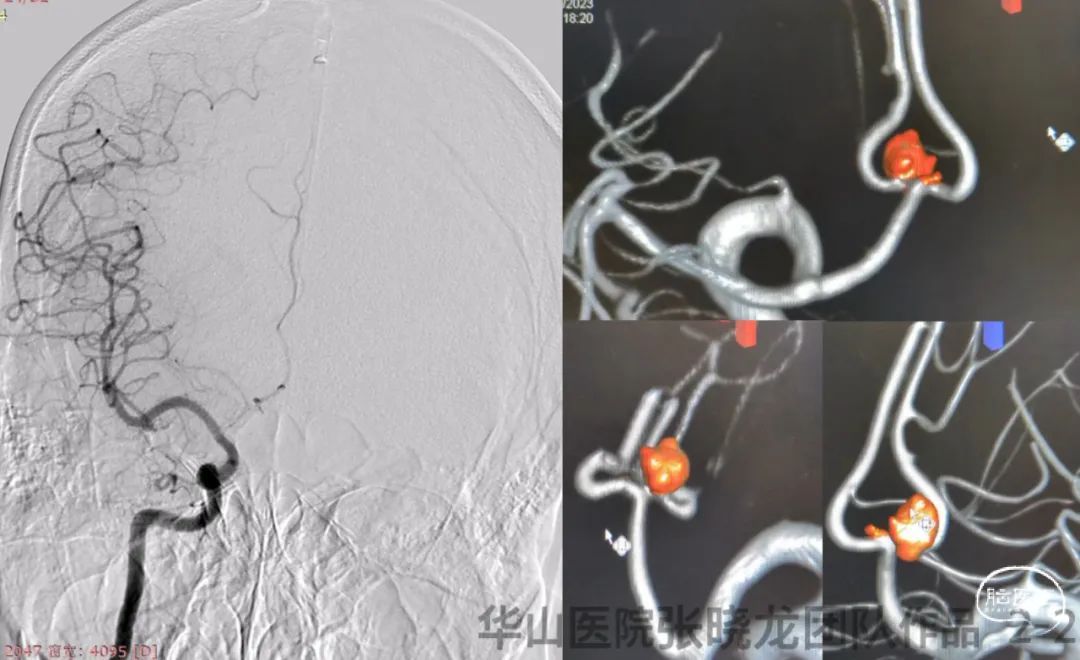

图 2 GIF. DSA和3D重建示左侧A2段不规则动脉瘤,旁边有一枚微小前交通动脉瘤。左侧颈内动脉颈段夹层,右侧A1段发育不佳。

• A tiny irregular anterior communicating aneurysm was treated by stent remolding technique because coils may be difficult to insert into. A Solitaire stent will be selected.

• Due to right A1 underdeveloped, the anterior communicating artery must be preserved.

• Left ICA cervical segment dissection can be treatment by a carotid stent.

• 前交通动脉微小不规则动脉瘤,弹簧圈填塞困难,计划采用Solitaire支架重塑作用治疗。

• 由于右侧A1发育不佳,前交通动脉必须保留。

• 左侧颈内动脉颈段夹层可采用颈动脉支架治疗。